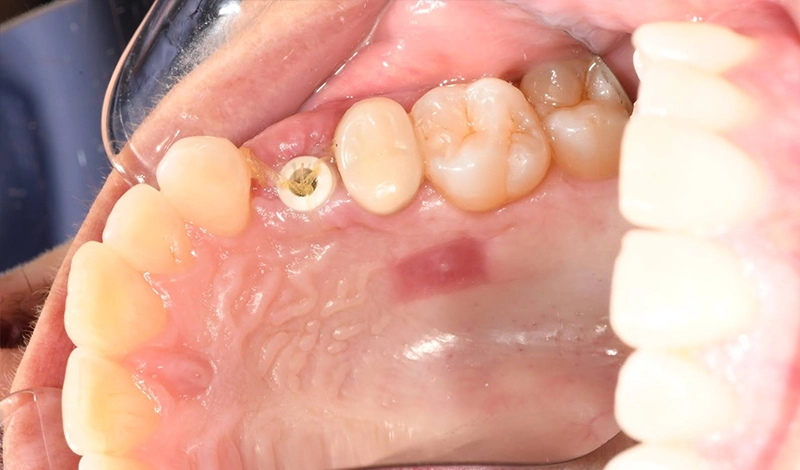

Upper (L) 1st premolar (missing):

The site showed significant soft-tissue loss, with reduced gum thickness and contour, making it unsuitable to support an ideal cosmetic implant without grafting.

A dental implant post was placed into the jawbone at the missing upper premolar site. A temporary crown/provisional was fitted over the implant. The provisional is shaped so the gum heals around it in a natural, scalloped form—this is the emergence profile.

- The grafted gum at the site demonstrates stable contour on review.